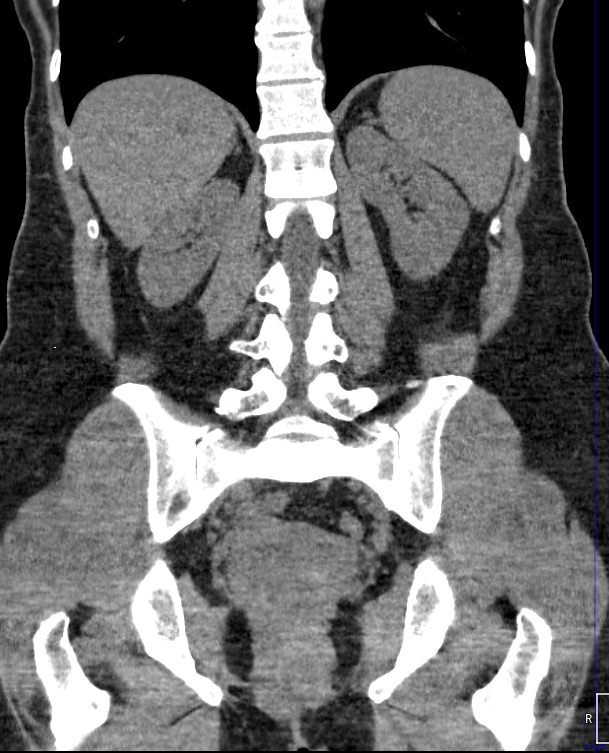

Методика КТ позволяет оценить анатомическое строение почек, надпочечников, состояние мочеточников и мочевого пузыря, кроме того, дает возможность визуализировать сосудистую систему и регионарные лимфатические узлы.

Сканирование применяется для выявления воспалительных заболеваний почек, чашечно-лоханочной системы, мочеточников и мочевого пузыря, также позволяет обнаружить конкременты на фоне мочекаменной болезни, диагностировать доброкачественные и злокачественные новообразования, точно классифицировать кистозные образования по системе Bosniak, что особенно важно для урологов и нефрологов, а также определить степень поражения регионарных лимфатических узлов. Кроме того, КТ используется для диагностики травматических повреждений органов мочевыделения, аномалий развития почечно-лоханочной системы, дает максимальную информацию для хирурга при планировании оперативного вмешательства.

Что показывает КТ почек, мочеточников, мочевого пузыря

- опущение почек;

- аномалии развития почек, мочетоников

- доброкачественные и злокачественные новообразования;

- камни (конкременты);

- уретероцеле

- сосудистую патологию (сосудисто-мочеточниковый конфликт, инфаркт почки);

- последствия оперативных вмешательств;

- увеличение лимфоузлов в брюшной полости, забрюшинном пространстве и малом тазу;

- травматические изменения

- патологии сосудов малого таза.